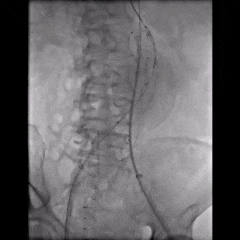

手术采用腹主分支支架,主体释放后行交叉腿髂支延伸。

造影示肾下腹主动脉瘤

选用28-14-140mm主动脉覆膜支架

释放短腿(交叉腿)

导丝超选右髂支

右侧延续16-18-140mm髂支

左侧延续16-18-140mm髂支

术中释放右侧髂支后,患者突发腹痛、心率增快、血压下降,造影怀疑右髂动脉破裂,紧急加放髂支并弹簧圈栓塞。